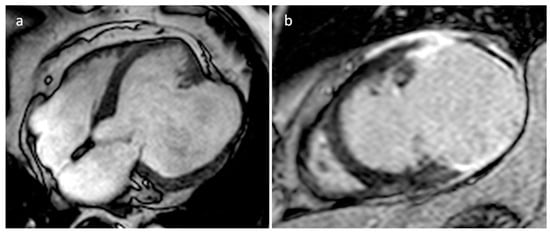

| Myxoma | Adulthood. Carney complex. | LA | Usually, asymptomatic. Rarely, intracardiac obstruction, embolic events and constitutional symptoms | Mobile mass arising from the IAS | Globular or spherical, with a friable surface and heterogeneous internal echogenicity | Heterogeneous, low attenuation, may be calcified | Isointense T1w, High T2w, heterogeneous LGE |